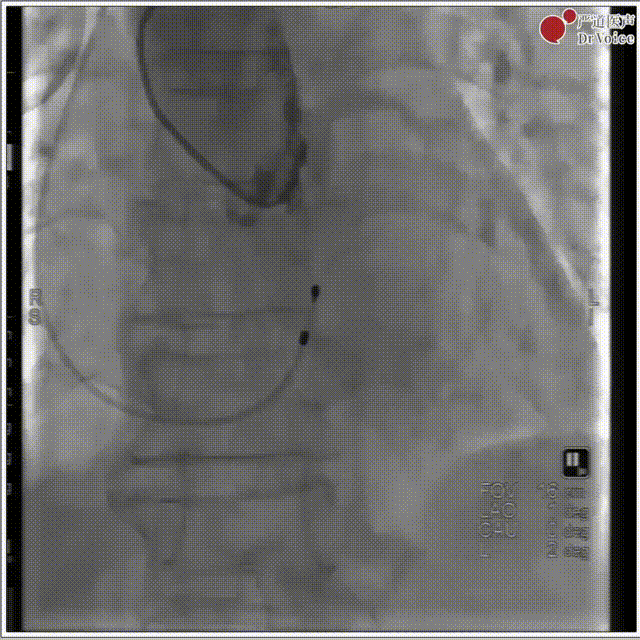

2. 冠脉保护,左冠预埋支架。

冠脉保护后造影